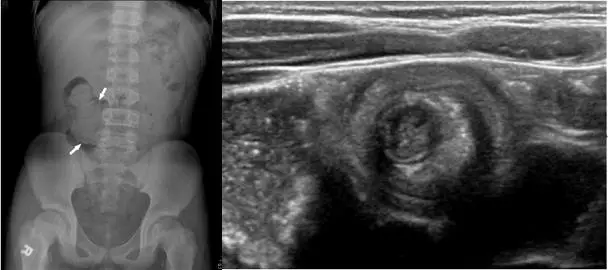

12歲的張小弟,近三日無正常解便,早上媽媽發現他解出黏液狀的排泄物,被家人送到急診室。醫師診察後安排腹部X光及腹部超音波檢查,如圖所示。張小弟最有可能罹患下列何者疾病? 圖片描述

小兒 intussusception(腸套疊)係指一段腸管被蠕動力量「套入」遠端腸管,造成機械性阻塞與腸系膜血流受限。典型臨床表現包含陣發性腹痛、嘔吐與黏液或帶血的「currant-jelly stool」。影像診斷首選超音波,縱切呈現 pseudokidney sign,橫切則見 concentric rings 的 target/doughnut sign;單純腹部 X 光常見右下腹腸氣缺乏或 crescent sign。(emedicine.medscape.com, radiopaedia.org)

影像分析:

1. 左圖(腹部 X 光):可見右側結腸區域腸氣明顯減少,箭頭所指之軟組織密度影兼有「meniscus/crescent」外弧,提示腸壁與被牽入之脂肪組織折疊;遠端結腸幾乎無氣體,符合機械性阻塞的「paucity of gas」表現,常見於腸套疊。

2. 右圖(腹部超音波橫切):中央為高度回聲腸系膜脂肪,被多層低、高回聲交替的腸壁環繞,典型「target / doughnut sign」,專屬於 intussusception,靈敏度、特異度皆接近 100%。(emedicine.medscape.com)

同時符合臨床「黏液血便」、X 光 crescent/paucity sign 及超音波 target sign;亦是兒童最常見急腹症之一。(radiopaedia.org)

腸套疊在 3 個月至 6 歲最常見;青少年雖較少見,仍可能因局部淋巴增生、Meckel diverticulum 或腸息肉成為 lead point。本案 12 歲男童三天未排便並解出黏液血便,腹部 X 光呈現右側腸氣缺乏及 crescent sign,超音波出現經典 target sign,三項診斷要素高度吻合 intussusception。故最佳答案為 D。